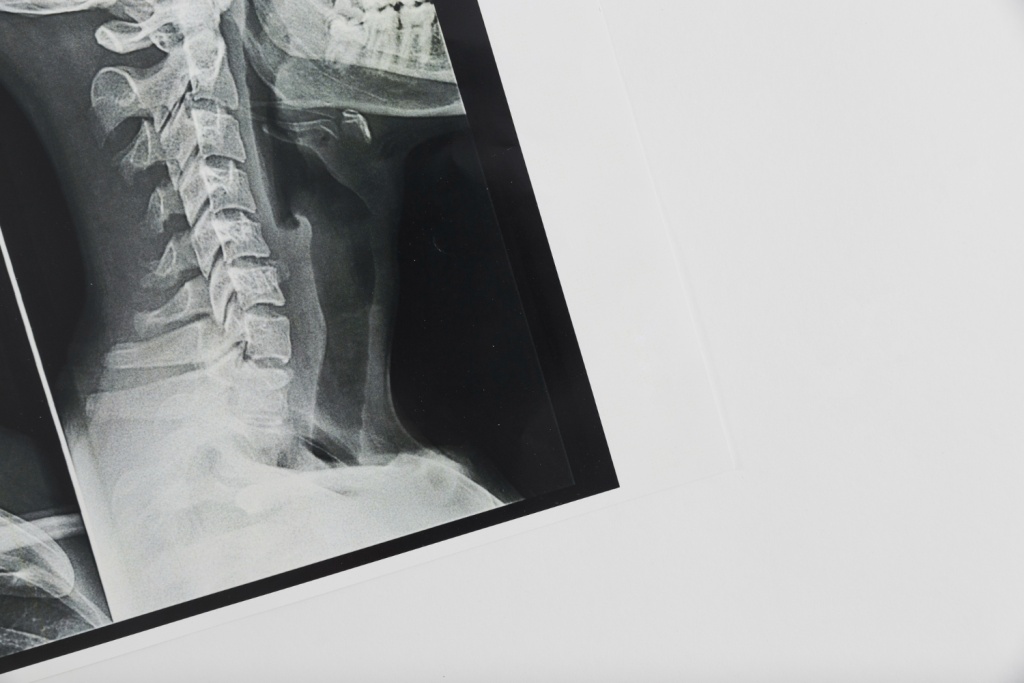

Фото: ru.freepik.com

6 мая. /MEDIA-TALK/.Рентген-установки типа С-дуга используют во время операций, чтобы врач мог проводить манипуляции под рентген-контролем. Изображение передается в реальном времени.